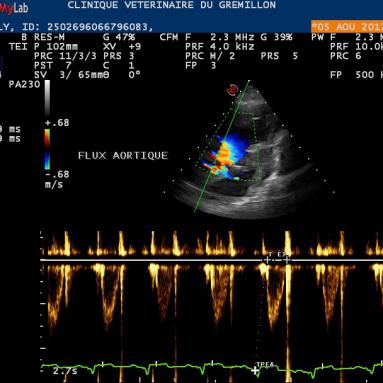

Les Modes Doppler:

Les modes Doppler servent à visualiser et à mesurer les vitesses des flux de sang. Ils sont au nombre de trois:

• Le Doppler Couleur: il permet de visualiser les flux de sang dans un organe, la couleur (bleue ou rouge) permet d'orienter le sens du sang.

• Le Doppler Pulsé: ce mode permet de mesurer la vitesse du sang en un point précis sur une ligne que l'on place et que l'on oriente à notre guise. Ce mode est surtout utiliser pour s'assurer de l'efficacité d'un flux sanguin ...

• Le Doppler continu: ce mode est le meilleur moyen pour mesurer la vitesse d'un flux sanguin orienté dans le même sens qu'une ligne que l'on va diposer et orienté à notre guise. Il est indispensable de placer cette ligne avec la même orientation que le flux de sang, une deviation de quelques degrés sous estimera la vitesse réelle du flux

Le résultat de ces mesures sont dépendantes de la qualité de la machine, des sondes et de l'expérience de l'opérateur.

Doppler Couleur

Doppler Pulsé

Doppler continu